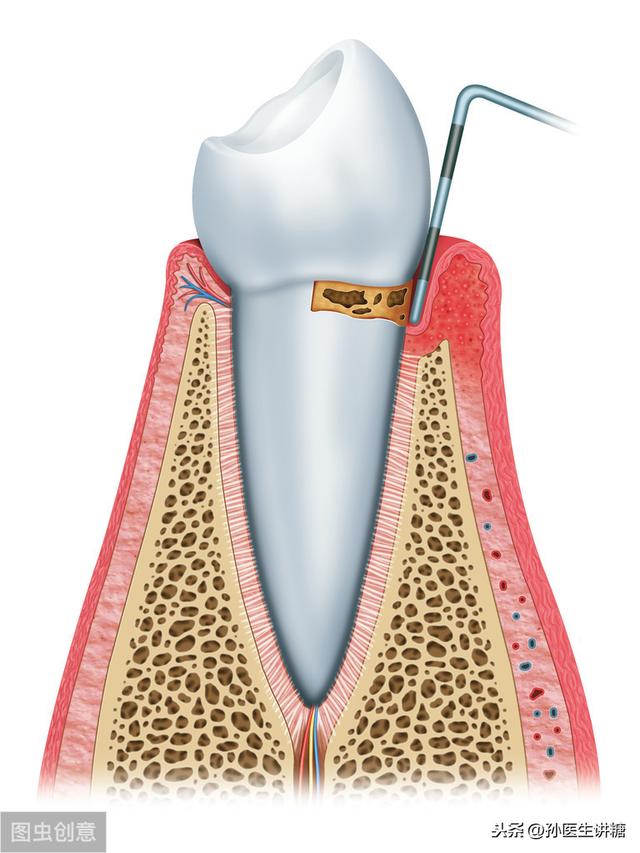

歯周炎は、歯垢に含まれる微生物によって引き起こされる歯周支持組織の慢性感染症であり、主に以下のような形で歯周支持組織に炎症と破壊をもたらす。歯周ポケットの形成、アタッチメントポイントの進行性喪失、歯槽骨の吸収糖尿病合併症は糖尿病患者に多く、糖尿病の慢性合併症のひとつと考えられている。

歯周炎の診断には、主に歯肉の炎症、出血、歯周ポケットの深さ、アタッチメントの喪失などが含まれる。

軽度の歯肉炎:歯肉に炎症があり、プロービングで出血する。

中等度の歯周炎で、歯肉の炎症、プロービング時の出血、膿性の分泌物、軽度の歯のゆるみを伴う。

重度の歯周炎になると、炎症がより顕著になったり、歯槽膿漏を起こしたりして、歯が抜けやすくなります。

まず歯周炎とは、プラーク(歯垢)による感染やその他の様々な要因によって、歯を支える組織(歯肉、歯根膜、歯槽骨、象牙質)が破壊され、炎症を伴う歯周ポケットの形成、アタッチメントの喪失、歯槽骨の吸収が起こり、重症になると歯を失う病気である。歯周炎は高度に蔓延した炎症性疾患として、宿主の全身の健康を脅かす可能性がある。